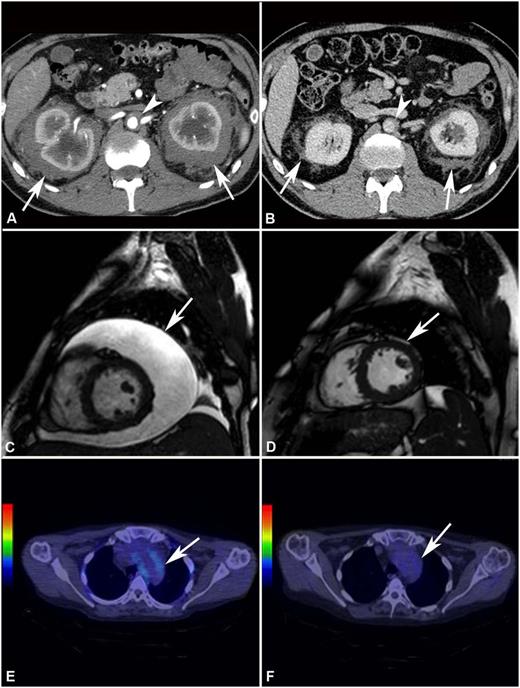

Response to treatment assessed by different imaging modalities. (A) Abdominal CT performed before treatment and (B) after 4 years of SRL and PDN treatment in patient #2. The scans show marked shrinkage of peri-renal (arrows) and peri-aortic fibrosis (arrowhead). (C) Cardiac MRI (T2-weighted, fat-saturation sequence, sagittal view) performed before treatment and (D) after 12 months of treatment with SRL and PDN in patient #10. The scans show neither recurrence of pericardial effusion (arrow) (the patient had also undergone pericardiocentesis) nor signs of pericardial infiltration. (E) 18F-FDG PET-CT performed before and (F) after 12 months of treatment with SRL and PDN in patient #10. The scans (axial view) show disappearance of 18F-FDG uptake at the thoracic aorta level (aortic arch) (arrow).